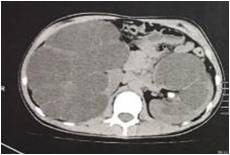

一期手术前,小花双肾重度积水

2017年10月28日,小花被省林业医院诊断为:1.右侧输尿管下段结石;2.左肾多发结石;3.双肾重度积水;4.右肾无功能。经过治疗,现肾功能恢复。两天后,小花也将走出医院,重返阔别已久的课堂。

2017年10月28日,小花的父亲带着她从老家渠县来到四川省林业中心医院泌尿外科。因为小花的腹部明显较大,这引起了副主任医师郭伟全的格外注意。“经仔细查体并完善常规检查后,我发现小花腹部长大的原因为右肾巨大积水所致,初步诊断:1.右侧输尿管下段结石;2.左肾多发结石;3.双肾重度积水;4.右肾无功能。”郭伟全说。